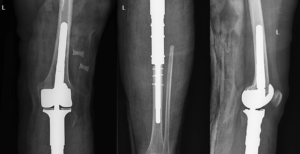

جراحی برای سرطان استخوان جراحی، بخش مهمی از درمان اکثر انواع سرطانهای استخوان میباشد. معمولا شامل موارد زیر است: بیوپسی برای تشخیص سرطان برداشتن تومور